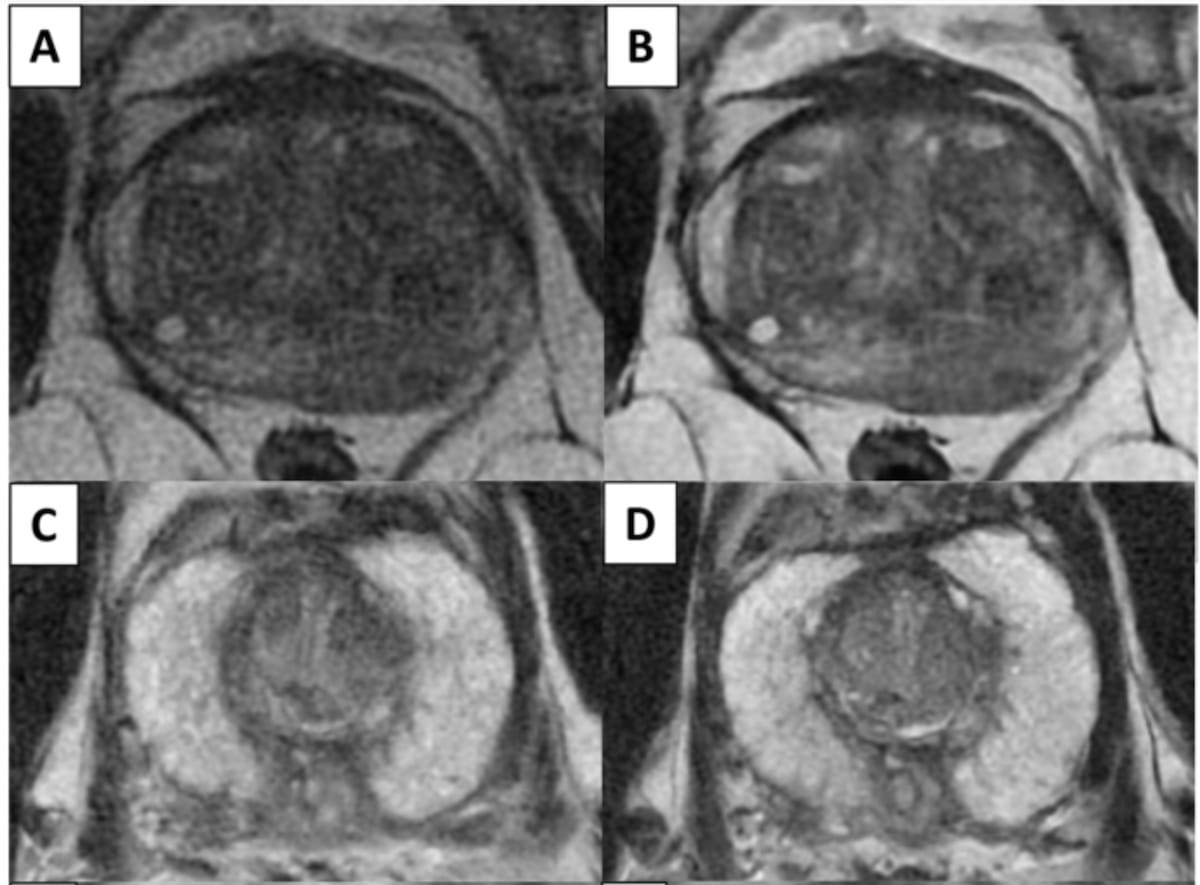

A model that combines multiparametric MRI findings with clinical factors may enhance the accuracy of predicting clinically significant prostate cancer and significantly reduce unnecessary systematic prostate biopsies in biopsy-naïve patients.